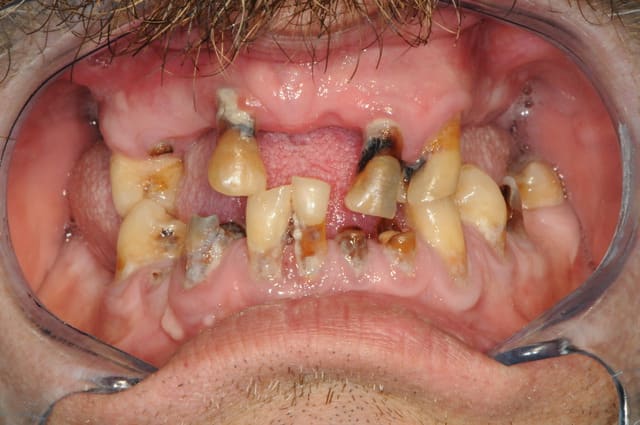

bon, je m'y colle...

j'suis sure que vous trouverez pas cette fois ci.

la meilleur solution c'est qu'il se laisse pousser la moustache, ça cache les chicots, ça tient chaud l'hiver quand les dents sont sensibles au froid, et ça coute pas trop cher en entretient.

pour d57 je dirais bridge 13 14 15 16 meme si je ne suis pas sur (la couronne en or c'est sur qu'elle est naturelle)

si c'est ça c quand meme super bien fait

tu y es presque...

et aussi bridge en bas sur implant ? 45 47

en haut, céram sur 13 et bridge / implants et en bas,

effectivement bridge sur implant, mais à partir de 44.

la patiente de 87 ans était super pressée d'avoir au moins une partie de terminée.

les implants du coté gauches ont été posés en même temps qu'à droite.

il me faut encore extraire 37 et refaire le bridge 24-26 avant de finir le bridge sur implant en bas à gauche.